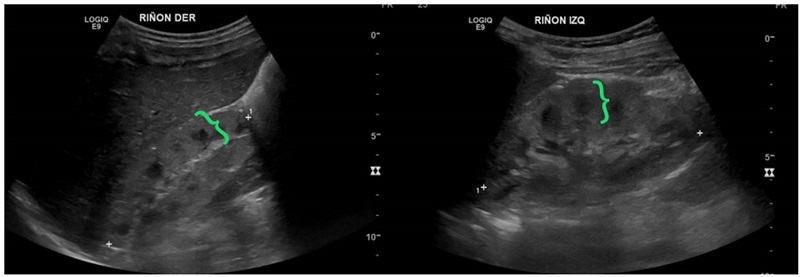

Se trató de un paciente de sexo masculino, con antecedentes de un hermano que falleció por síndrome hepatorrenal y cuya valoración se inició a los nueve meses de edad por elevación de las transaminasas y ecografía abdominal que evidenció cambios sugestivos de hepatopatía crónica. Posteriormente, se identificó compromiso renal mediante imágenes que mostraron alteración de la ecogenicidad renal y signos de nefropatía crónica (figura 7). A los dos años, progresó rápidamente a enfermedad renal crónica en estadio V y fue sometido a trasplante hepatorrenal a los tres años. Se realizó secuenciación de exoma clínico que detectó la variante patogénica c.2571_2574del p.Ser857Argfster4, homocigota en el gen NPHP3, lo que confirmó el diagnóstico de nefronoptisis de tipo III, de herencia autosómica recesiva. En su último control, a los cuatro años de vida, tenía un adecuado crecimiento y buena función del injerto renal, sin hipertensión arterial.

Análisis. La nefronoptisis es una enfermedad renal tubulointersticial de herencia autosómica recesiva 27. Se caracteriza por la presencia de nefritis tubulointersticial crónica, de quistes en la unión corticomedular y progresión a falla renal antes de los 30 años, de hecho, es la primera causa de enfermedad renal terminal en las primeras décadas de la vida 28-30. Además, del 10 al 20 % de los casos pueden estar acompañados de manifestaciones extrarrenales o presentarse en el contexto de otras ciliopatías. Según la edad de aparición de enfermedad renal terminal, se clasifica en infantil, adolescente o juvenil 28,31. Se han descrito más de 25 genes relacionados con nefronoptisis; el más frecuente es NPHP1 (nefrocistina 1), presente en 20 a 25 % de los casos. En 60 a 70 % de los casos, no se encuentra una causa genética 28.